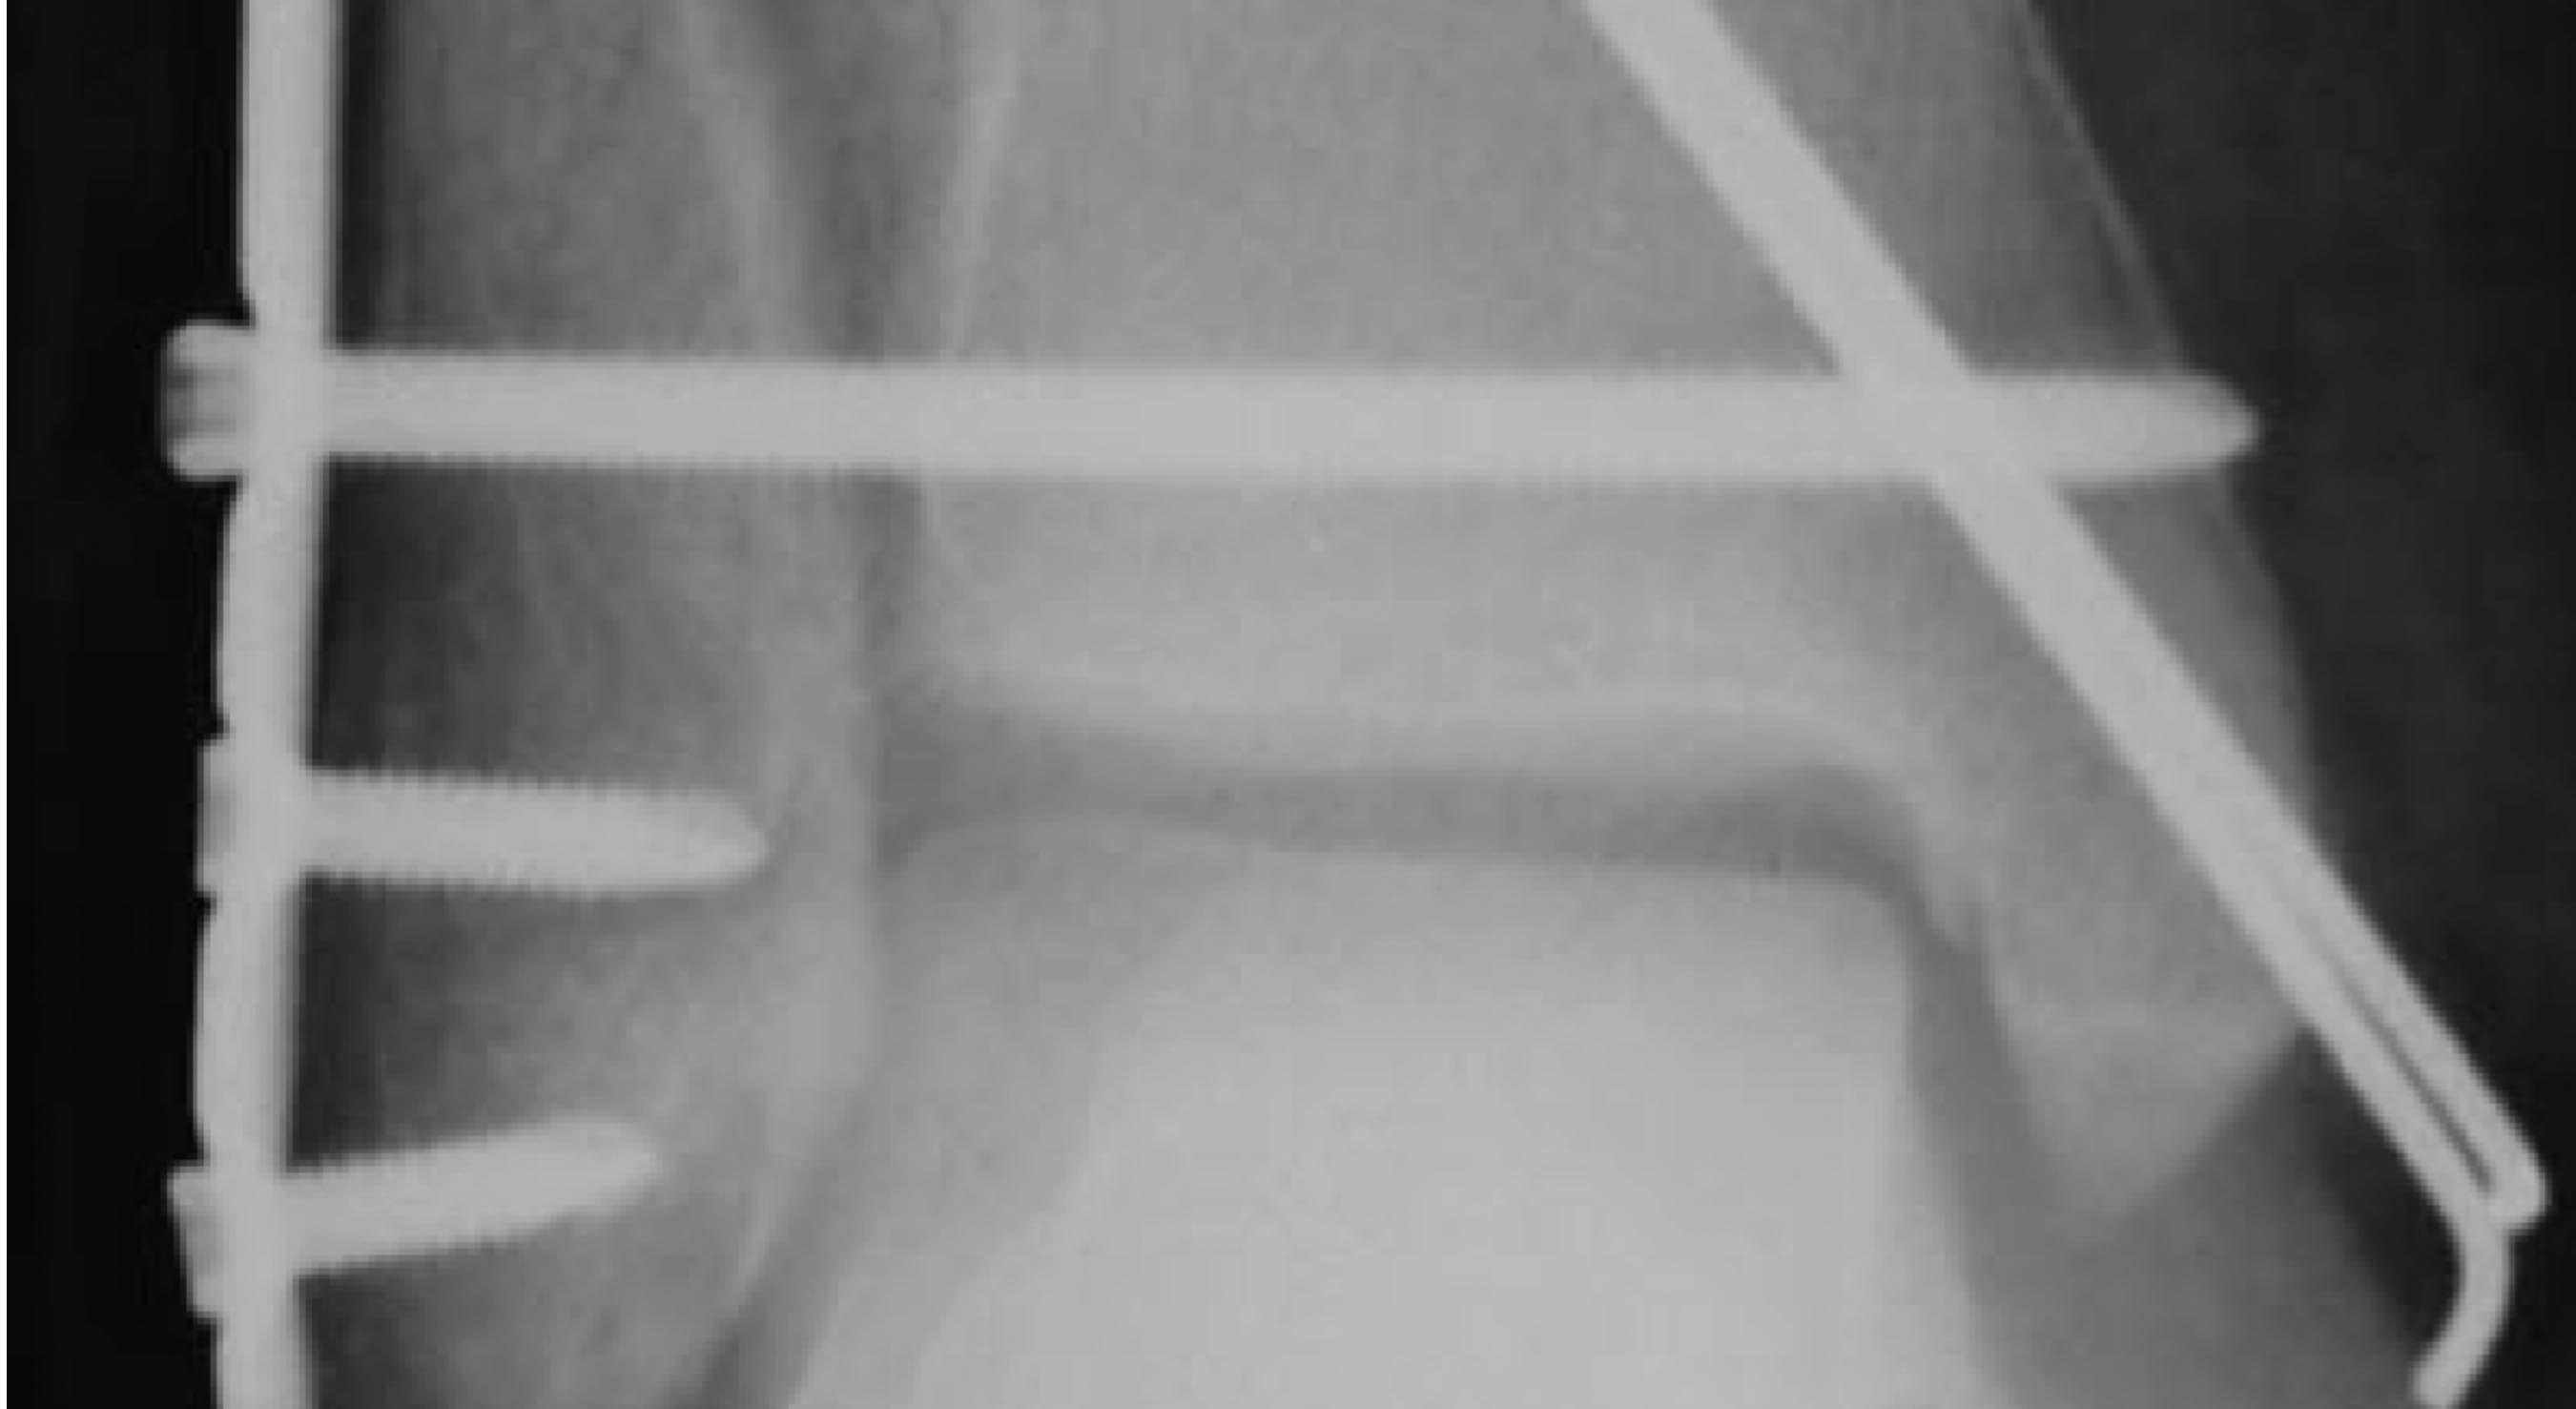

НЕ-НЕ! Это не кортикальный винт!!! Это 3,5 мм LHS self-tapping c

гексагональным шлицем (413.0хх) (см. приложение)